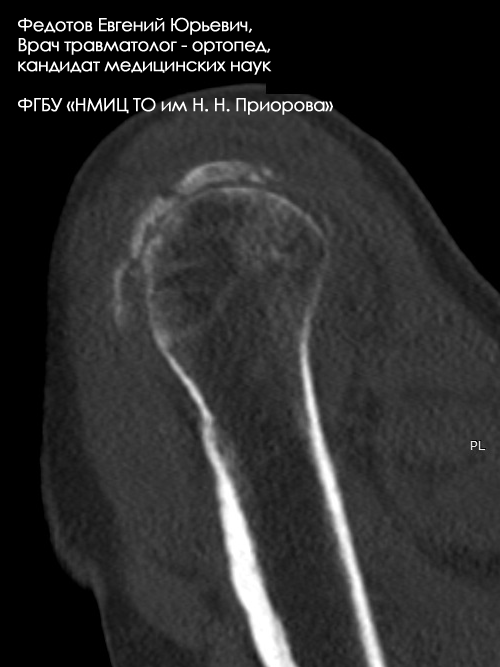

Пациентка с оскольчатым переломом верхнего отдела плечевой кости.

Рентгенограмма до операции.

Выполнена операция: металлоостеосинтез плечевой кости высокотехнологичным стержнем Targon.

Гипсовая повязка после операции не применялась, сразу после операции начата физкультура для суставов и мышц конечности.

Результат через 3 дня после операции.

Еще не сняты швы, виден отек, кровоподтеки на конечности после перелома. Пациентка уже может выполнять несложную бытовую работу, обслуживать себя без посторонней помощи.